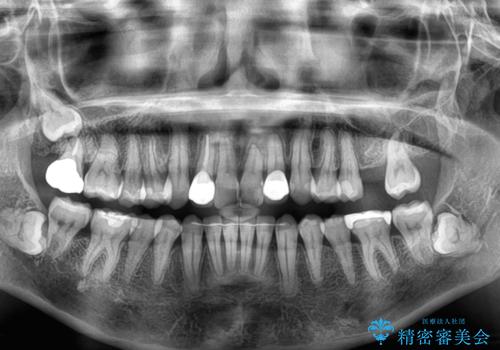

- 前歯のセラミッククラウンの縁が見えることが気になってから、デコボコも気になるようになってきたとのことで来院された患者様です。

デコボコの程度は中等度であったため、インビザライン・モデレートパッケージにて歯列を整えることとしました。

セラミッククラウンの装着されていた前歯と、大きな修復治療の跡がある反対側の歯は、矯正治療後に補綴治療を行うこととしました。

奥歯の欠損はインプラント、ブリッジ、入れ歯のどれにすれば良いかを決められず、仕事が非常にお忙しいこともあり、保留としたまま治療を終えることとなりました。

後戻りのリスクがあるため、なるべく早めに欠損補綴治療を開始する予定です。